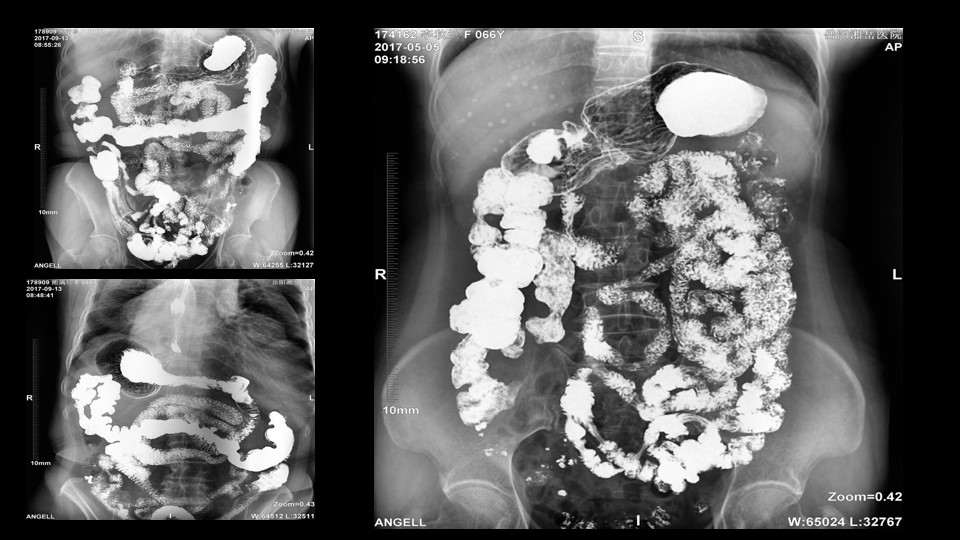

会议开始,岳阳市医学会放射分会副主委、湘岳医院放射科蔡雨主任,结合自身在放射影像的20多年经验,为参会嘉宾分享了动态DR在消化道造影中的应用价值。作为动态DR用户,蔡雨主任结合动态DR的实际拍片与操控经验,分享了动态DR技术在相关群体疾病检查上的独到优势和人文关怀。蔡雨主任说到:“随着内镜技术的发展以及CT、MR的发展,消化道造影在减少,但是这并不意味着消化道造影的价值在下降。以老年人为例,很多老年群体都患有严重的心肺疾病、或者消化道畸形,很多老年人本身就有糖尿病、高血压等等综合疾病,传统内镜的检查对于这类群体来说是一件难以忍受的痛苦,而动态DR的多项创新技术让这类群体的消化系统疾病筛查变得更为人性和精准。任何一个好的消化道造影,一定是患者、诊断医生、临床医生三方满意的结果。尊龙凯时人生就是博科技动态DR技术利用900万像素高清拍片、大幅面透视、高清点片、视频保存与回放等核心功能,完全满足临床对消化道气钡双重造影检查的需要。图像质量全面超越以往模拟胃肠机、影增数字胃肠机”。蔡雨主任全面演示了动态DR在食道造影、上消化道造影、小肠双对比造影、结肠气钡双对比造影中的应用,通过动态DR可以清晰获得临床诊断和评估的图像依据。

▲蔡雨主任使用动态造影图像示例